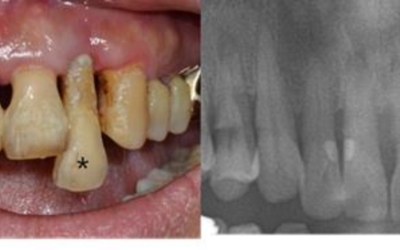

치은염에서 발전된 형태의 잇몸 염증 질환을 말합니다. 치은염이 잇몸 겉에 염증이 생긴 정도라면 치주염은 잇몸 겉에서 잇몸 뼈 주변까지 염증이 진행된 형태입니다. 따라서, 치은염보다 치료기간도 길어질 수밖에 없고 회복도 더딘 편입니다. 치주염은 치은염에서 발전된 형태이기 때문에 초기에는 양치질을 할 때 피가 나는 등의 치은염 증상을 겪게 돼요. 이후 치주염으로 발전한 초기에는 잇몸이 붓고 들뜬 느낌이 들며 붉어지고 건드렸을 때 출혈이 발생하게 돼요. 중기에는 잇몸이 내려가며 이 사이가 뜨기 시작해 치아가 조금씩 흔들리게 되고 말기에는 잇몸이 심하게 내려가 치아가 많이 흔들리게 돼요.

사랑니는 치아 중 아래 위로 가장 안쪽에 나오는 어금니입니다. 사람마다 사랑니가 4개가 나는 경우가 있고 1개가 나는 경우가 있으며, 잇몸이 붓고 아플때는 사랑니가 근처 어금니를 건드리는 잘못된 형태로 자라고 있을 확률이 높습니다.

잘못된 형태로 자라는 사랑니는 초기엔 잇몸이 붓는 정도이지만, 나중에는 근처 어금니를 썩게 만들고 사랑니와 멀쩡한 어금니까지 통째로 발치하게 되는 불상사가 발생할 수 있어요. 사랑니의 경우 잇몸 안쪽으로 매복해 자라는 경우도 많기 때문에 치과에서 사랑니 유무를 확실히 확인할 수 있어요.